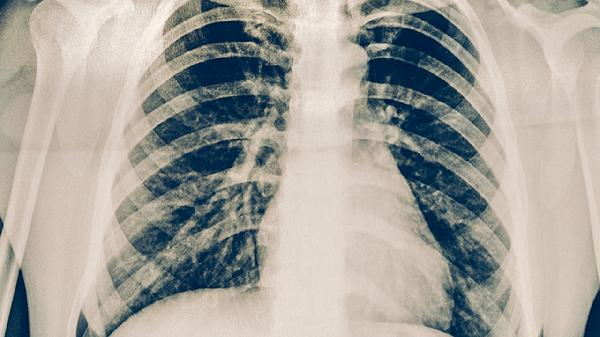

耐药肺结核的症状与普通肺结核相似,但可能更严重且治疗反应差,主要症状包括长期咳嗽咳痰、咯血或痰中带血、午后低热与夜间盗汗、胸痛与呼吸困难、以及进行性体重减轻和乏力。

四、胸痛与呼吸困难

胸痛和呼吸困难常出现在病变范围较广或累及胸膜时。胸痛多为病变部位的隐痛或钝痛,深呼吸或咳嗽时加重。呼吸困难则在肺部病变广泛导致肺功能受损,或出现大量胸腔积液压迫肺组织时发生。耐药肺结核因治疗不彻底,病灶容易扩散,更易引起胸膜炎或导致肺组织广泛破坏,从而引发明显的呼吸系统症状。治疗需针对病因,在抗结核治疗的同时,对于胸腔积液可能需要进行胸腔穿刺引流,并加强呼吸功能支持。